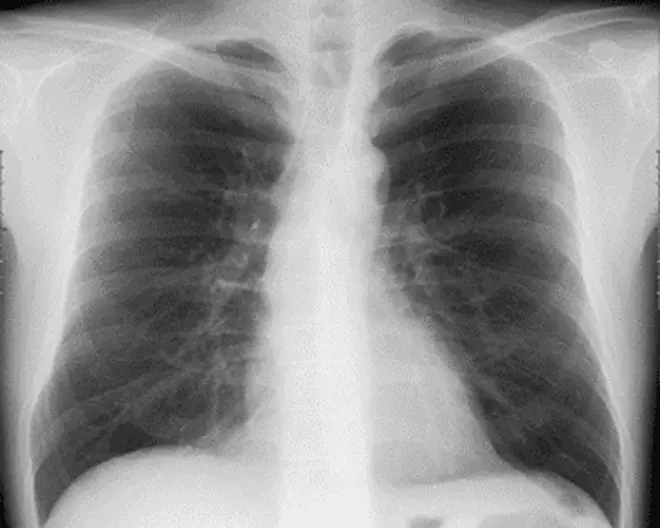

Seeds Clinic新宿三丁目では、CT装置を使った超低被ばく肺がん検診を実施しています。一般的な肺がん検診で行なわれる胸部X線検査(胸部レントゲン)では、骨との重なりで病気がわかりにくかったり、影が薄く小さいと見えにくいことがあります。CT検査ではこのような影が薄かったり、小さいタイプのがんでも見つけることができます。

レントゲン画像では影はほとんど見えませんが、CTでははっきりと映っているのがわかります。また、レントゲンでは心臓や横隔膜に隠れている場所もCTではしっかり見ることができます。胸部X線検査ではX線を使っての撮影となりますので、被ばくがあります。人間ドックなどで胸部X線撮影を正面と側面の2方向撮影をすると、約0.15mSv(シーベルト)の被ばくになります。日本での宇宙や大地、食物や空気中に存在する天然の放射性物質からの自然放射線による被ばくは1年間で約2.1mSvです。低被ばくでありながら、精度の高い検査が可能です。